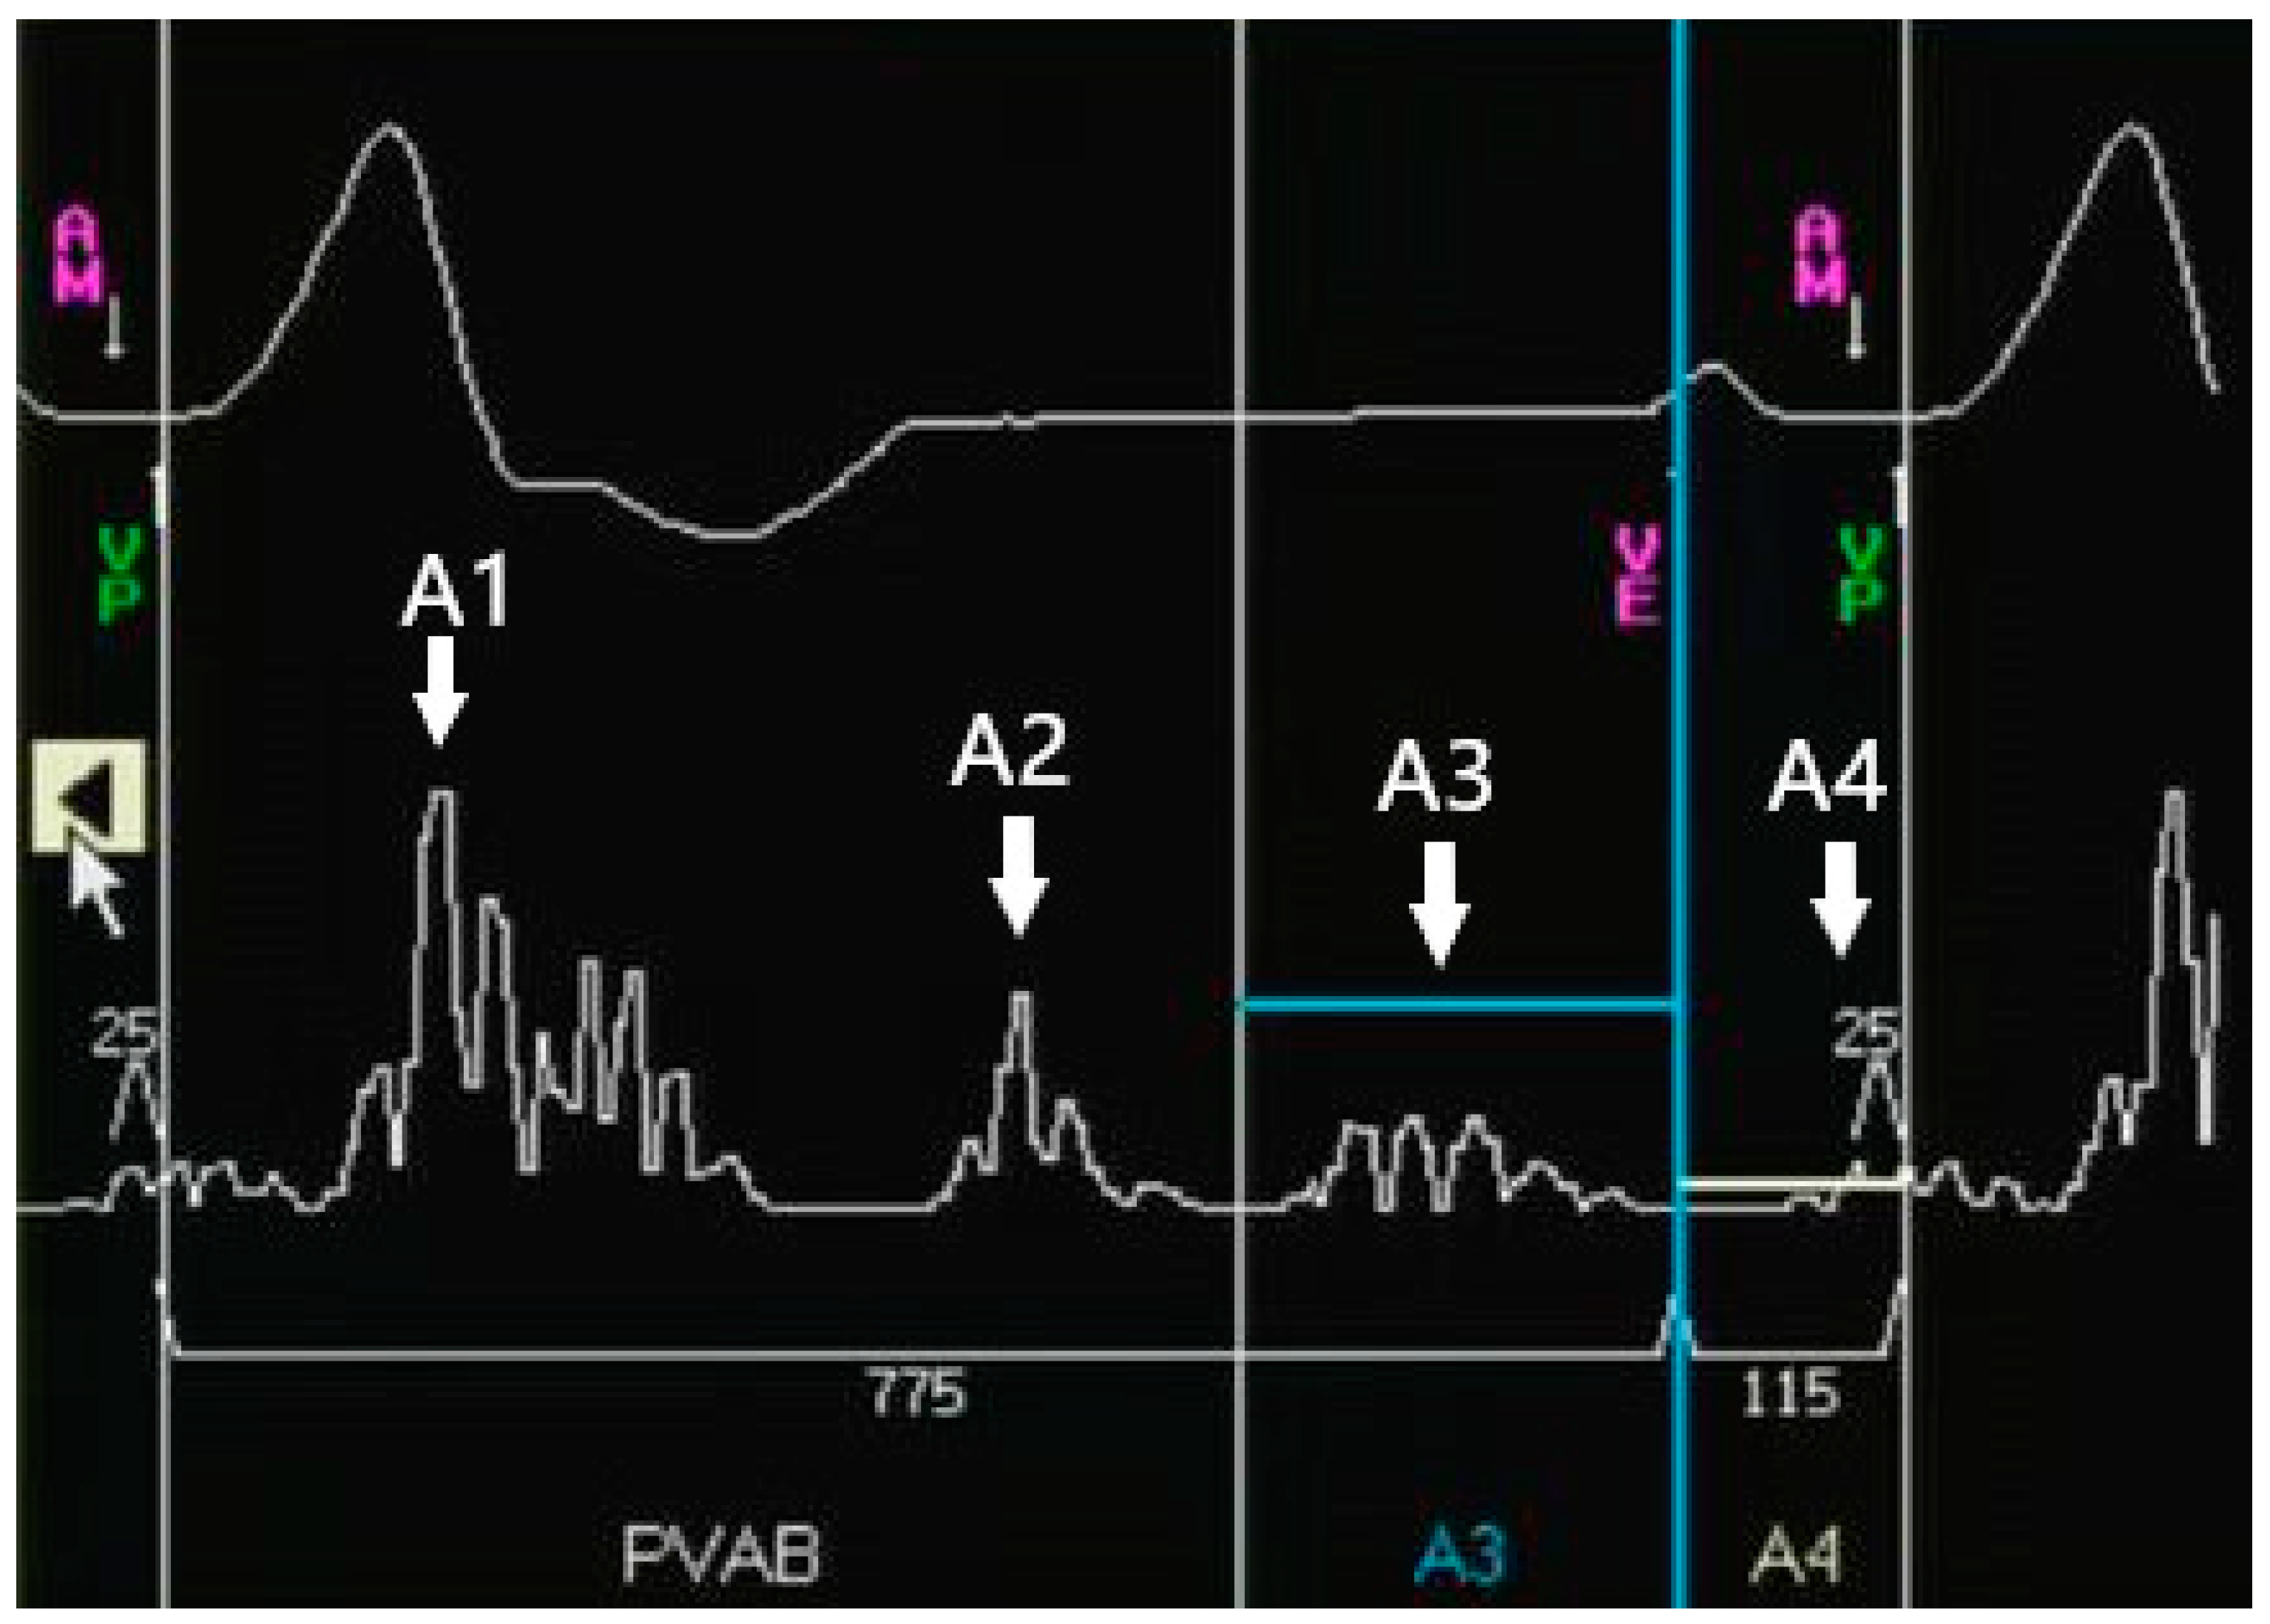

- Device programming: The nominal values of the Micra AV were optimized for patients during resting. Regular postimplant device reprogramming is necessary and should be individually optimized. The manual atrial mechanical (MAM) test is to line up A1–A4 signals with the corresponding surface ECG signals (Figure 2). Firstly, the MAM test with “auto” atrial mechanical features turned-off runs in the VDI mode to allow a clear distinction of the A1–A4 signals, and subsequently, MAM test runs in the VDD mode to make adjustment based on the track of atrial activity. The systematic and stepwise approaches including MAM test and adjustments of the A4 threshold, A3 window, and A3 threshold are to accurately discern A4 [78,79].

- The A4 threshold: In situations of low A4 amplitudes, a lower A4 threshold facilitates a reduction in the under-sensed A4 and improves the AV synchrony [72,73]; Meanwhile, in the case of low A4 amplitudes, the device’s built-in 3-axis accelerometer atrial-sensing vectors can be changed from a selection of one or two vectors to a recruitment of all three vectors to improve AV synchrony at the cost of negative impact on battery longevity [78,79]. When the A4 threshold is too low, the over-sensed A4 could impair the AV synchrony, which was observed in a study in which a higher A4 threshold was found to be related to a higher AV synchrony [74] (Figure 3A);

- The A3 window end: In situations of sinus tachycardia, the A4 signal falls in the A3 window, which reduces the AV synchrony. A shorter A3 window end interval for detecting the A4 signal and improving the AV synchrony has been confirmed in multiple studies [72,73,74]. A rate-dependent A3 window may be promising for tracking atrial contractions at higher heart rates. However, some researchers have suggested setting the A3 window below 700 ms and deactivating the automatic adjustment to improve the AV synchrony [74] (Figure 3B);

- The A3 threshold: In situations of sinus tachycardia, the A4 signal begins with the encroachment into the A3 window; however, as the heart rate is further elevated, the A4 signal could merge with the A3 signal and the A3 auto threshold function could result in the under-sensing of A4. Turning the A3 auto threshold function off and fixing the A3 threshold contribute to AV synchrony, and this is especially suitable for elevated sinus rates of 80–110/min [71]. A lower A3 threshold could improve the AV synchrony [74,76] (Figure 3C);

- The PVAB: In situations of Wenckebach behavior, the progressive shortening of the RP interval means that the P wave falls in the PVAB period, which results in the intermittent loss of A4 [76]. Shortening the PVAB to minimize the p-wave blanking is recommended. Wenckebach behavior occurs in patients with intrinsic conduction for whom the AV synchrony is high; therefore, the benefit of shortening PVAB is limited (Figure 3D);

| Heart Sound | Echocardiography | Electrocardiogram | ||

|---|---|---|---|---|

| A1 | Mitral/tricuspid valve closure | S1 | At the end of QRS complex | |

| A2 | Aortic/pulmonic valve closure | S2 | At the end of T wave | |

| A3 | Early passive ventricular filling | S3 | E wave | Before the onset of the P wave |

| A4 | Atrial contraction | S4 | A wave | After the inscription of the P wave |